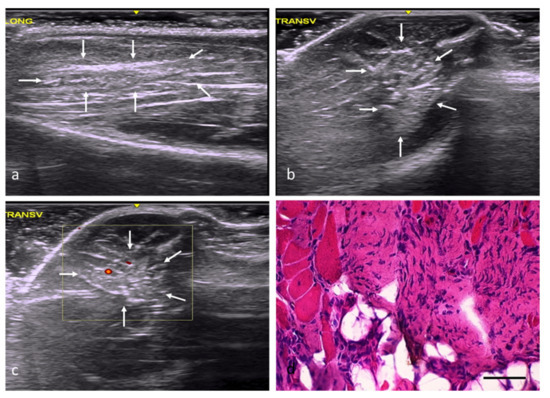

| Group | Identification of the Lesion | Edges of Lesion | Morphology of the Lesion | Increased Echogenicity | Echotexture Distortion | Vascularization |

|---|---|---|---|---|---|---|

| NC | — | — | — | Grade 0 | Grade 0 | Grade 0 |

| RC | Yes | poorly delimited | imprecise | Grade 1 | Grade 1 | Perilesional Grade 2 |

| FC | Yes | well delimited | angulated | Grade 3 | Grade 3 | Intralesional Grade 2 |

| AT | Yes | poorly delimited | imprecise | Grade 2 | Grade 1 | Intralesional Grade 1 |

| OS | Yes | well delimited | Variable (rounded, angled, or patchy) | Grade 3 | Grade 3 | Perilesional Grade 1 |

| DM | Yes | well delimited | Variable (rounded, angled, or patchy) | Grade 2 | Grade 3 | Intralesional Grade 1 |